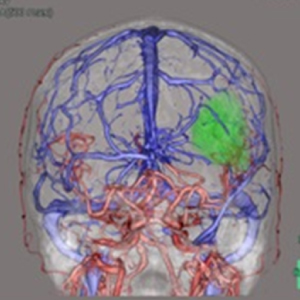

検出器の多列化により短時間に広範囲の撮影が可能となりました。また1度の撮影で様々な断面画像を得られます。得られた画像をワークステーションで解析することで3D画像を作成できます。

造影剤を使用することで病変や血管を詳細に描出できるため病変部の血管走行を把握することができます。血管走行の3Dは手術プランに役立てられます。- 腰部血管3D

- 頭部動静脈3D